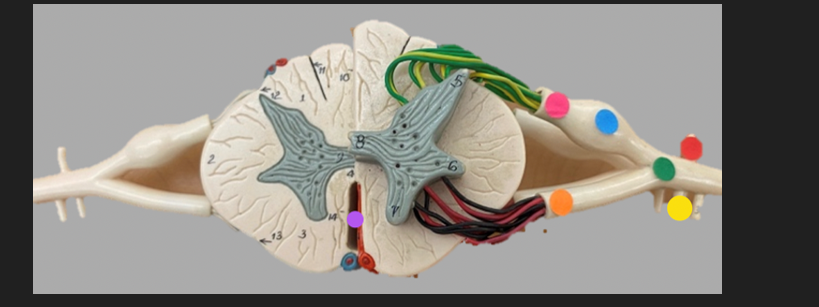

green dot

spinal nerve

orange dot

ventral root

pink dot

dorsal root

blue dot

dorsal root ganglion

red dot

dorsal ramus

yellow dot

ventral ramus

purple dot

anterior median fissure

red dot

posterior (dorsal) horn

purple dot

lateral horn

dark blue dot

anterior (ventral) horn

orange dot

dorsal column

yellow dot

lateral column

dark green

anterior column

line green and pink doit

gray commissure

light blue dot

posterior median sulcus